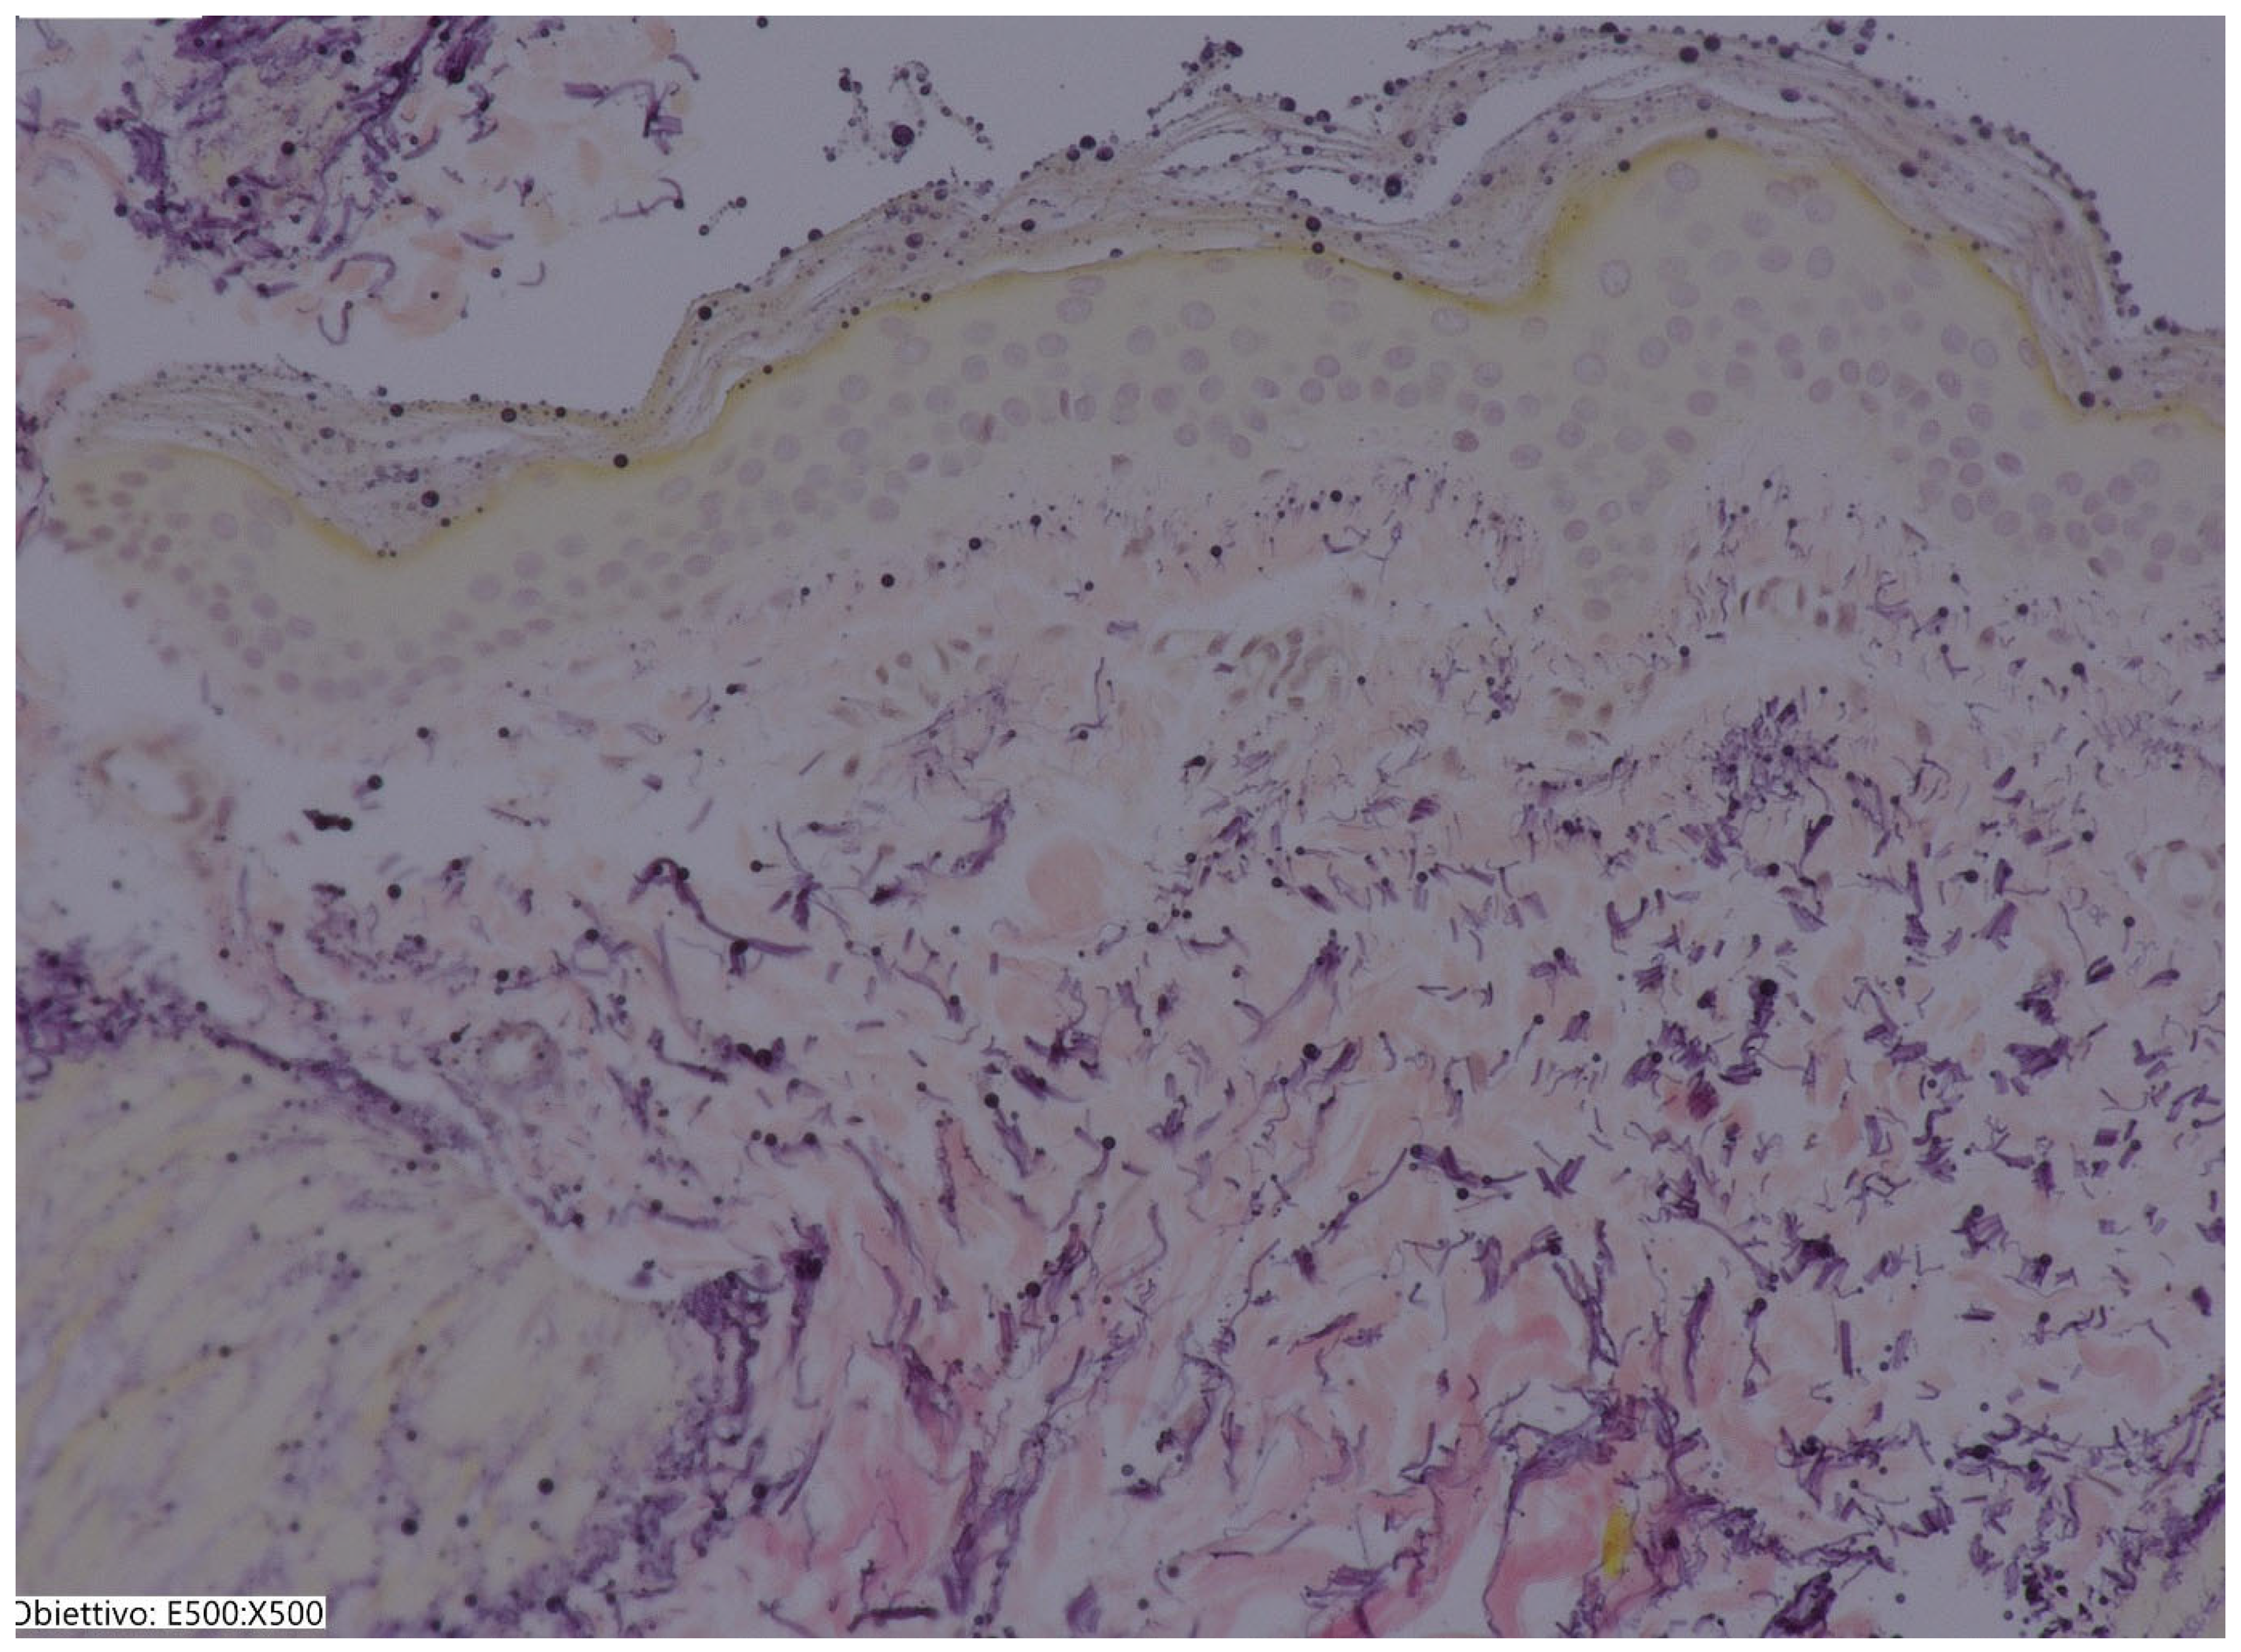

2. Material and Methods

3.2. Histological Results